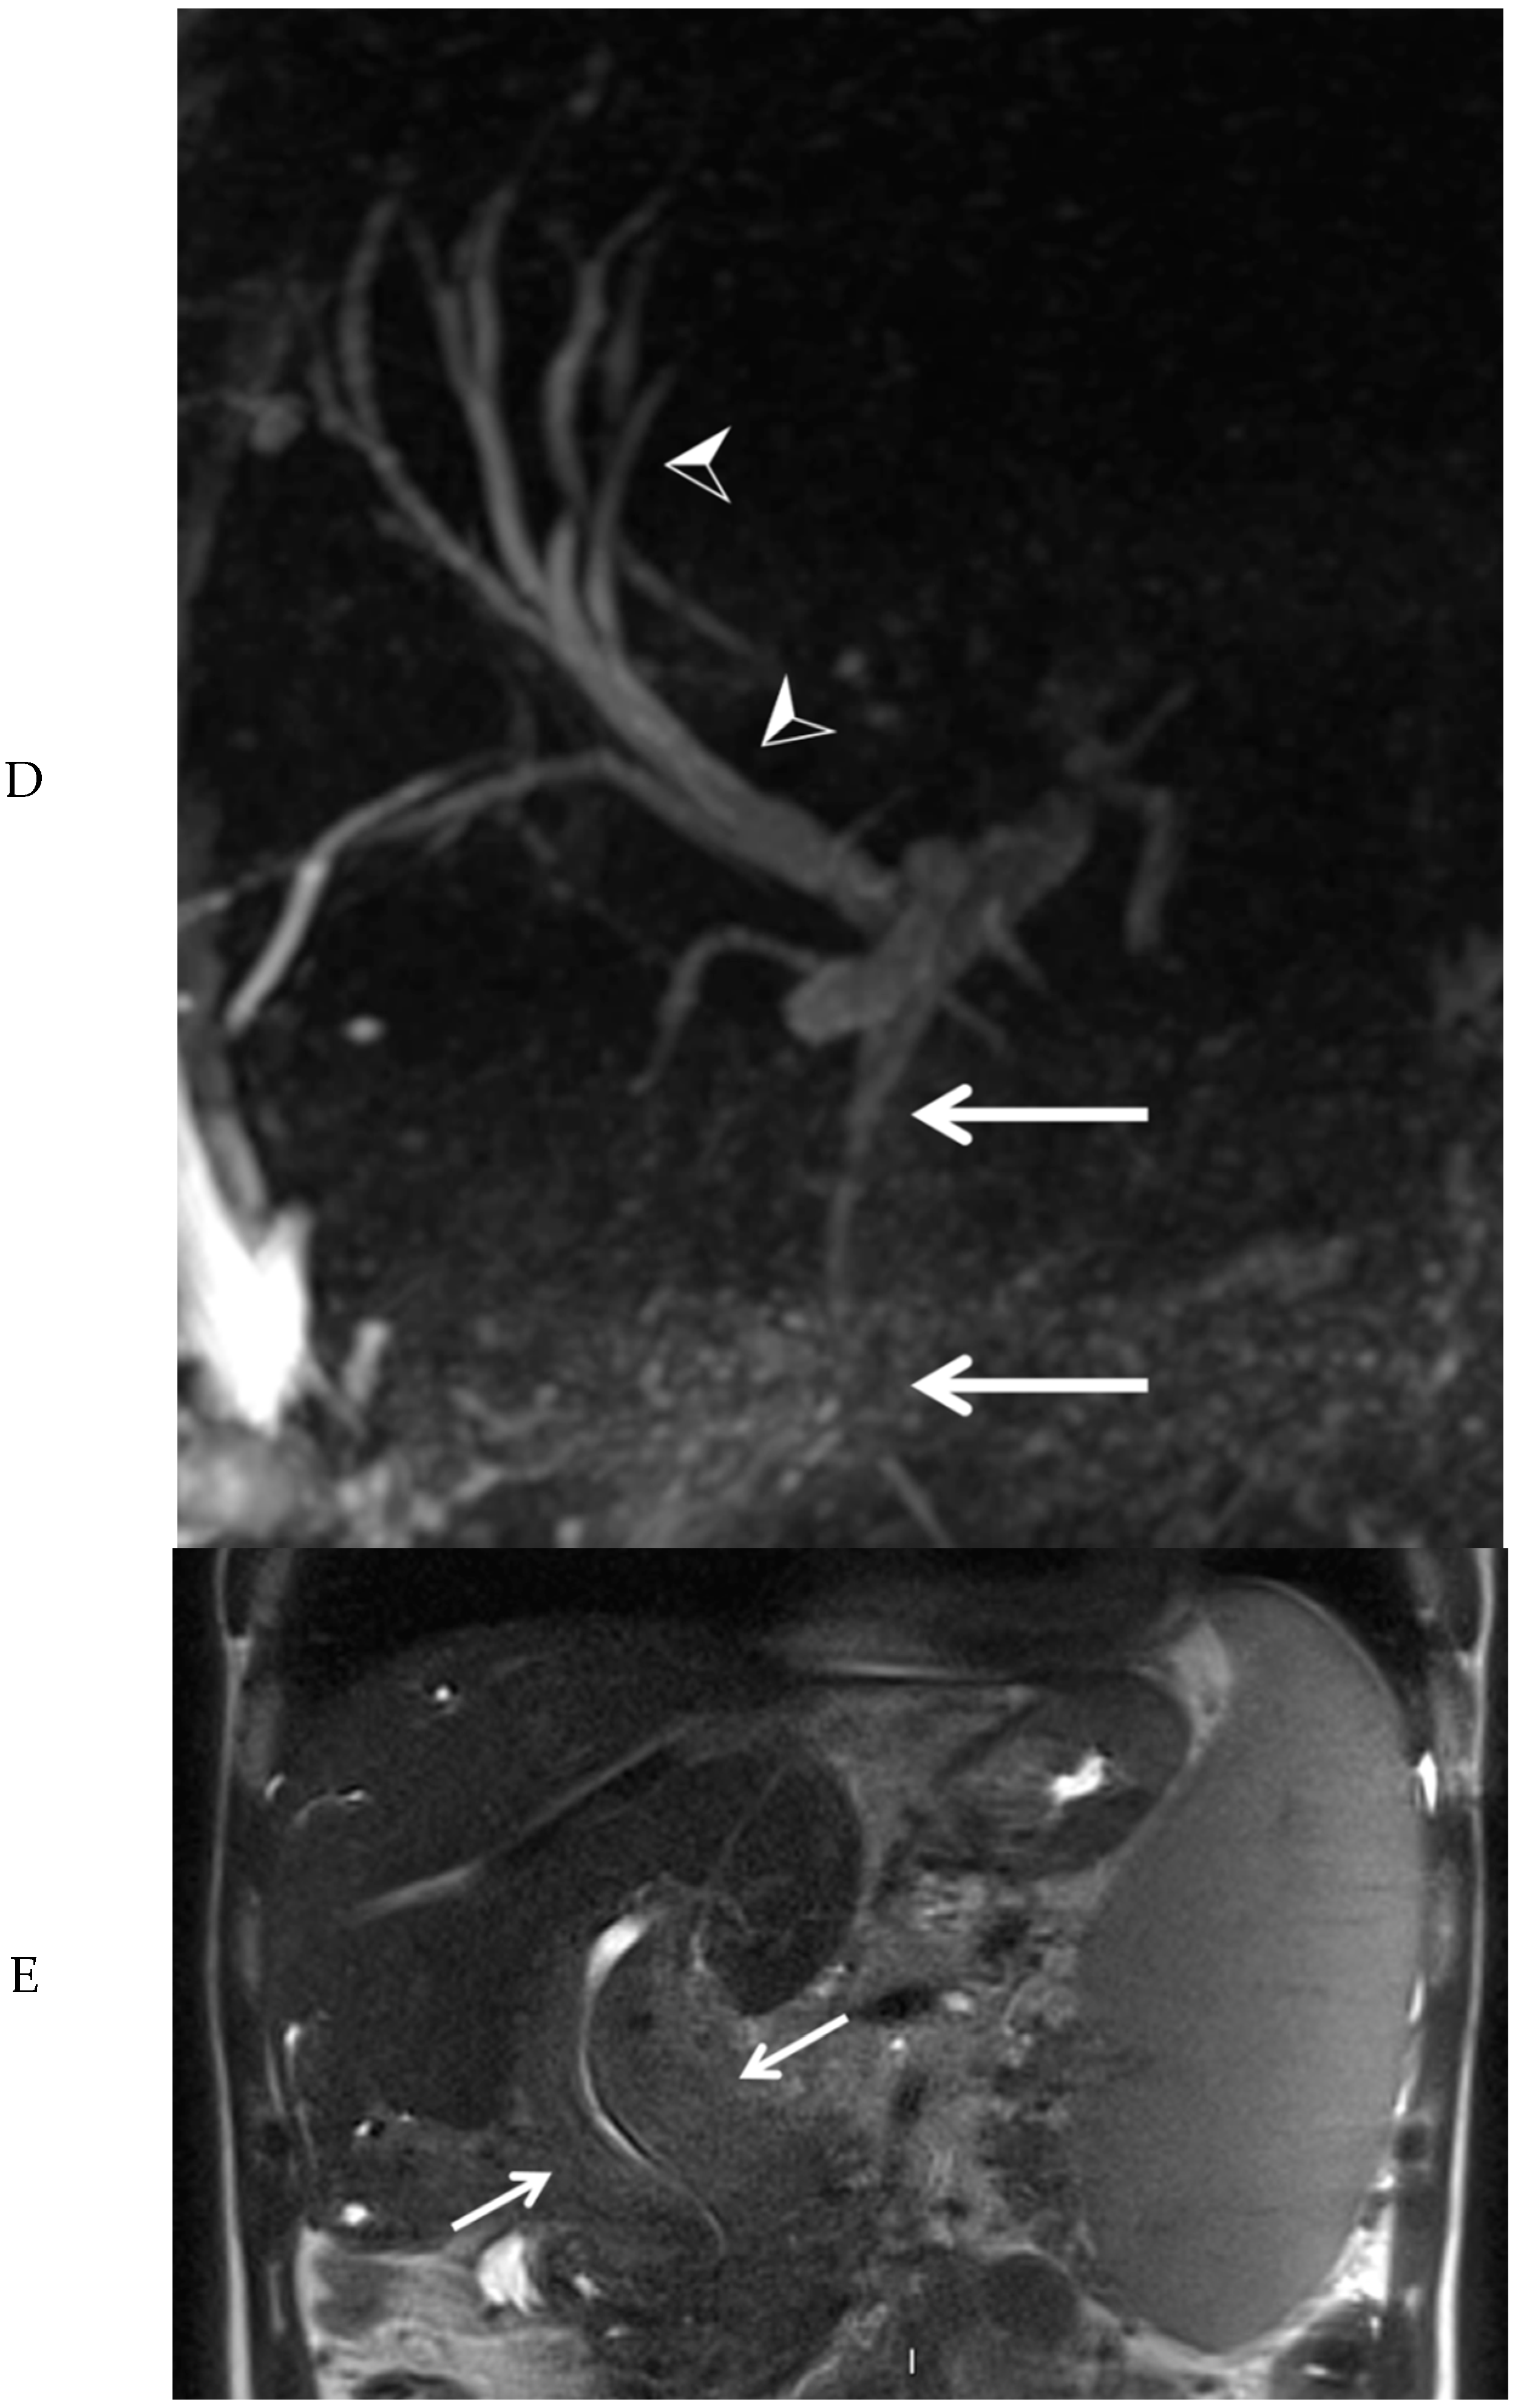

Subsequently, EUS combined with fine needle biopsy, and MRI of the upper abdomen were performed. EUS showed a highly vascular mass with a benign aspect. EUS-guided fine needle biopsy was somewhat difficult due to hardness of the mass. The histopathologic findings were most consistent with a lesion of vascular origin, such as hemangioma. MRI of the upper abdomen revealed a large mass surrounding the common bile duct, central intrahepatic bile ducts, cystic duct, and gallbladder, without diffusion restriction. After administration of intravenous contrast medium, no enhancement of the mass was visible in the arterial phase (Figure 3A). However, many small vessels were visible within the mass in the portal venous phase (Figure 3B), with diffuse homogeneous enhancement of the mass in the delayed phase (Figure 3C). At the MRCP, narrowing of the common bile duct was visible along its complete course, combined with dilation of the intrahepatic bile ducts (Figure 3D). At T2-weighted imaging, the mass around the narrowed common bile duct was slightly hyperintense when compared to the liver parenchyma (Figure 3E).

Figure 3.

Magnetic resonance imaging of the mass in the upper abdomen (arrows). Shown are T1 weighted subtraction images of the mass in the upper abdomen with fat suppression after administration of intravenous contrast medium in the arterial (A), portal venous (B), and delayed phase (C). At magnetic resonance cholangiopancreaticography, narrowing of the common bile duct is visible along its complete course (arrows), combined with dilation of the intrahepatic bile ducts (arrowheads) (D). At T2-weighted imaging (E, coronal view), the mass surrounding the narrowed common bile duct was slightly hyperintense, when compared to the liver parenchyma (arrows).